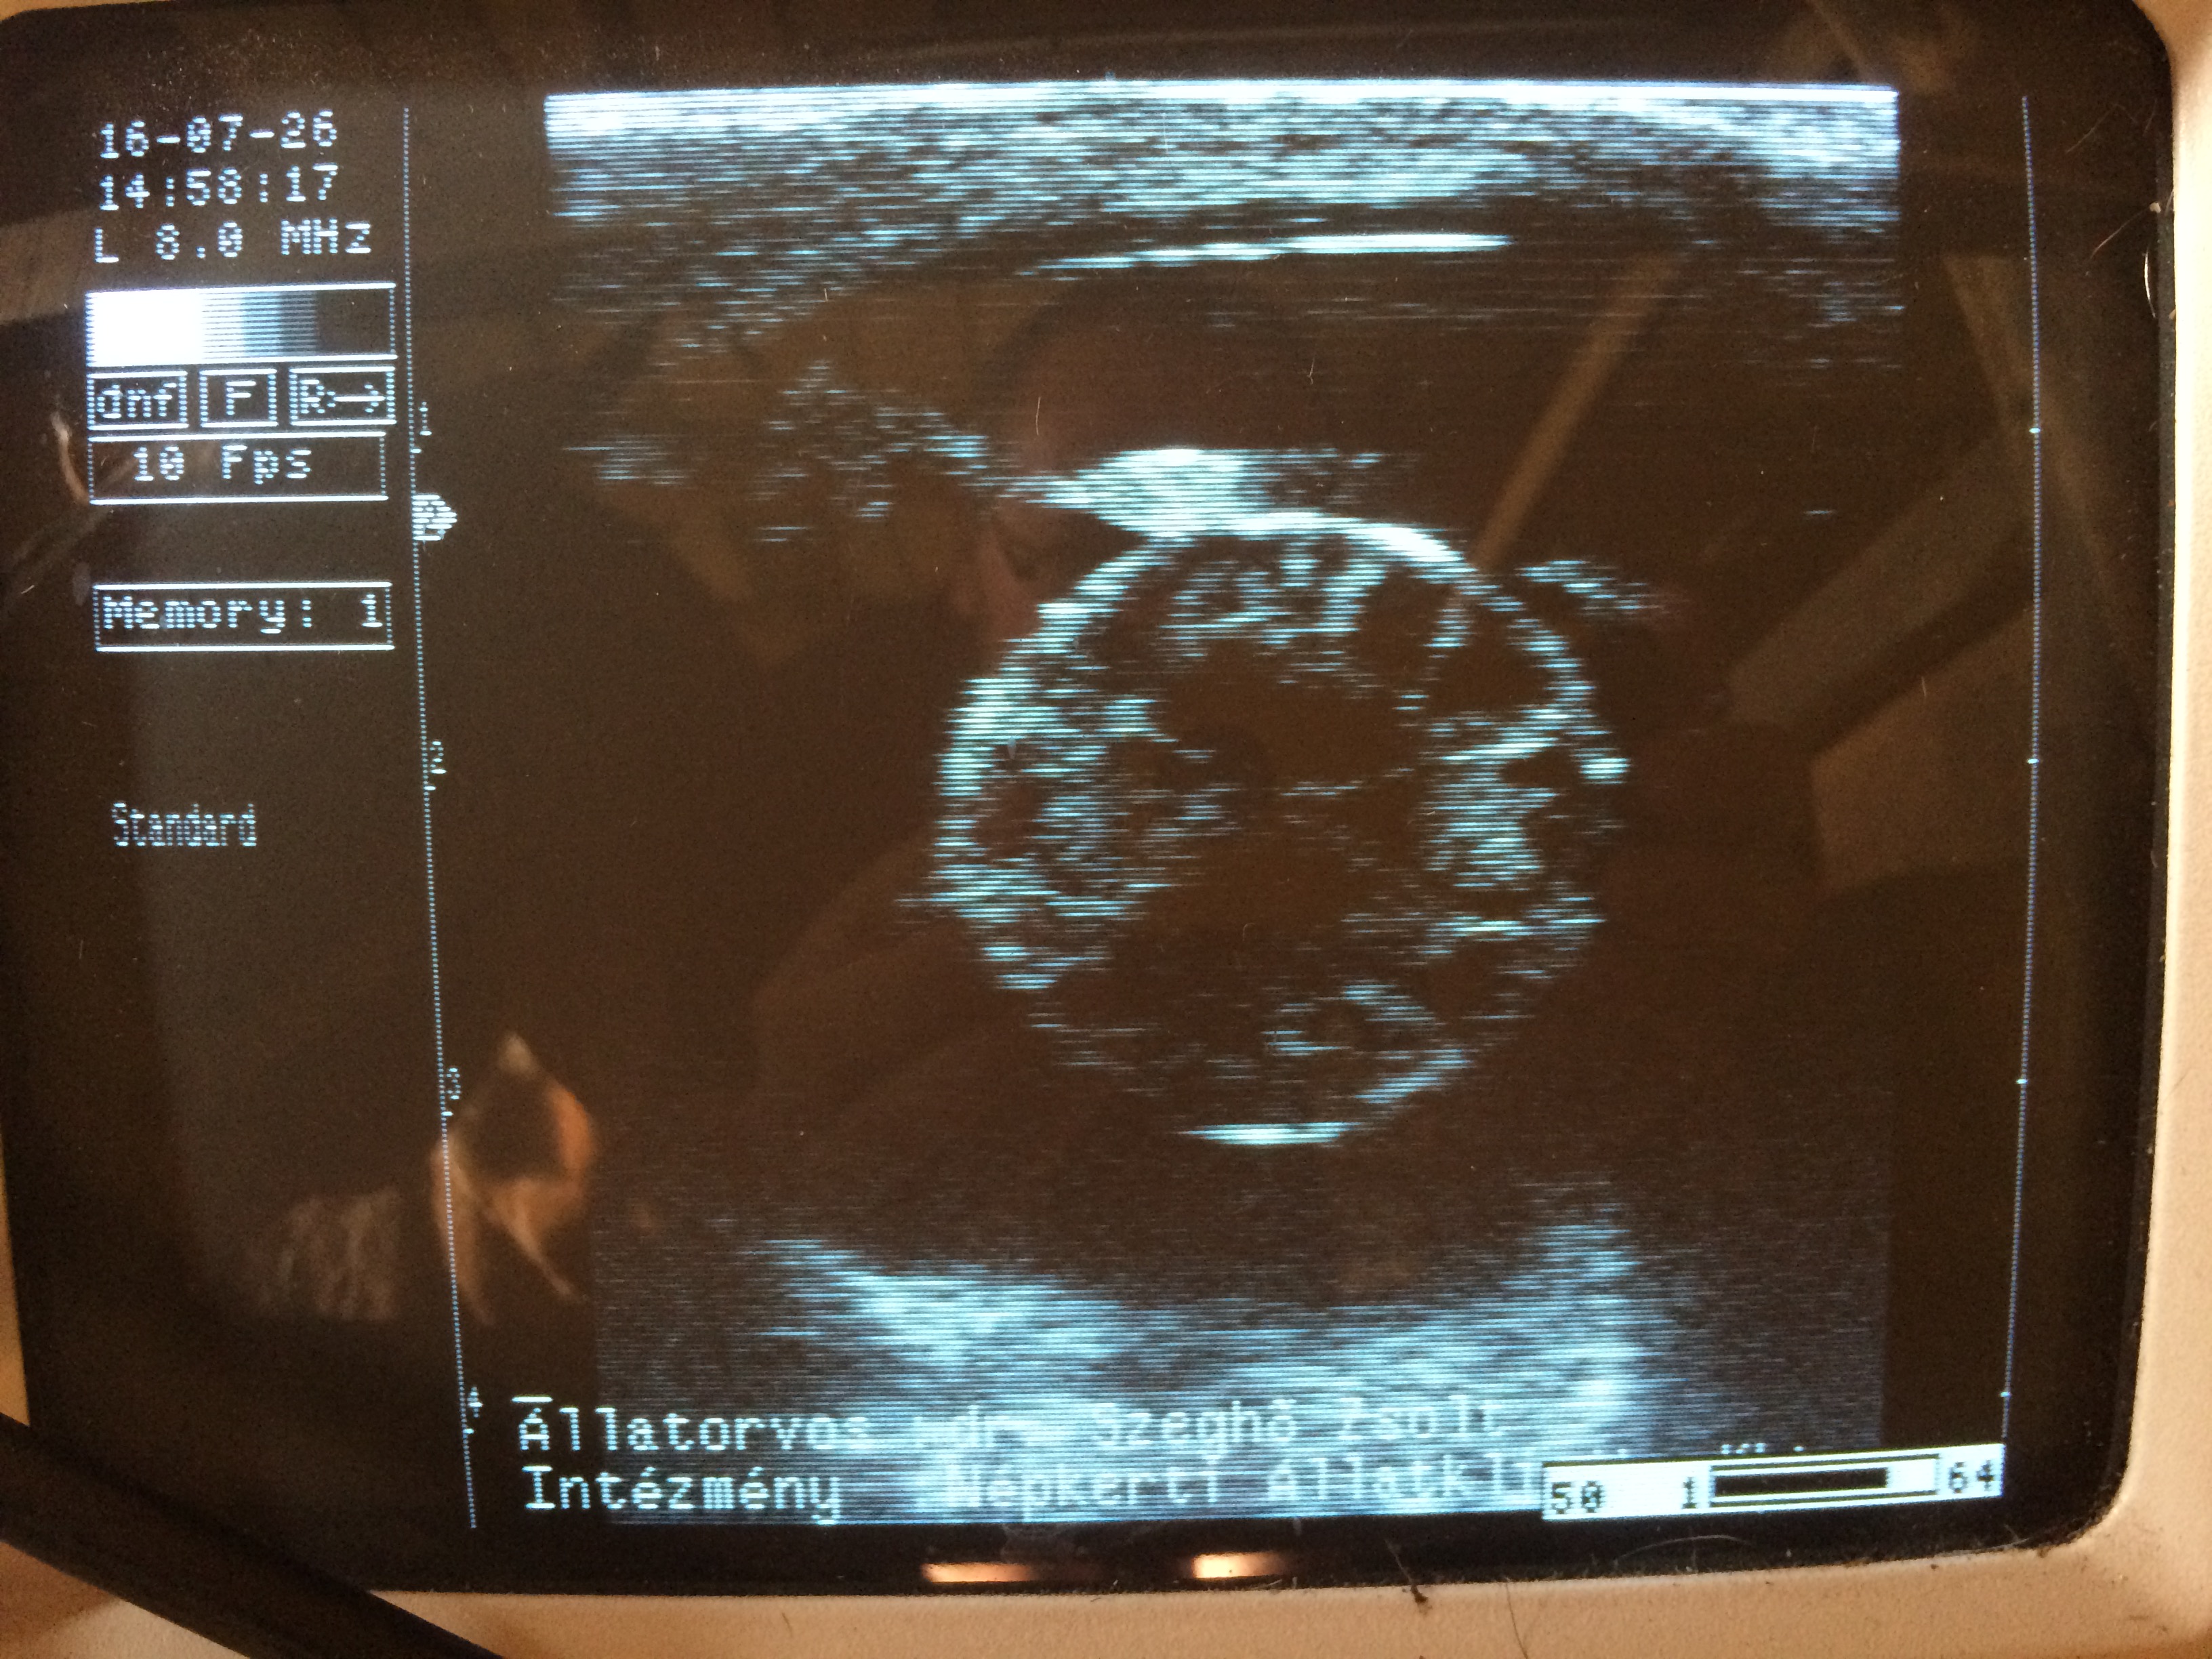

Szemészeti ultrahang